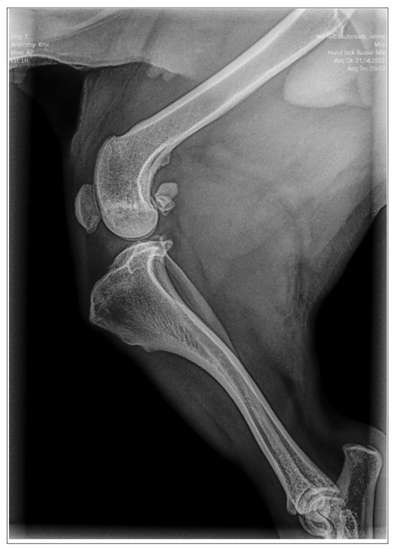

Hallo, bei unserer Mila (Jack-Russel-Mischling, 9 Jahre, 11 Monate) wurde vor einigen Wochen der Verdacht auf Anriss des Kreuzbands am linken hinteren Knie ausgesprochen. Das war in einer Klinik, in der auch eine Röntgen-Aufnahme gemacht wurde. Uns wurde zur TPLO-OP geraten, die dort in der Klinik durchgeführt würde. Unser TA hatte uns mit einem anderen Verdacht (Spondylose) an die Klinik zur Abklärung überwiesen. Waren danach noch bei einem anderen TA für eine 3. Meinung. Der Anriss könnte theoretisch sein, könnte aber auch eine beginnende Arthrose sein. Wenn es das Kreuzband ist, würde der 3. TA ein neues Band einsetzen. Es wurde uns erst mal zur intensiven Schonung geraten, um zu sehen wie sich das Knie entwickelt. In der Tat ist es jetzt sogar deutlich besser. Werden die nächste Woche vermutlich nochmal zur Kontrolle hingehen. Ich frage mich nun, FALLS doch eine OP anstehen sollte, ist eine TPLO besser als ein Bandersatz? Was sind die Unterschiede der Methoden bzw bei unserem Hund (ca 35 cm groß, Gewicht 9,5 kg) eher zu empfehlen? Dass eine Klinik „gerne“ operiert, hatte ich bei dem Termin durchaus auch festgestellt. Danke für eure Meinungen!

In der Klinik wurde eine Röntgen Aufnahme gemacht. Welche Bandersatz-Methode der 3. TA durchführen würde, muss ich klären. Ich wusste nicht, dass es da unterschiedliche gibt.